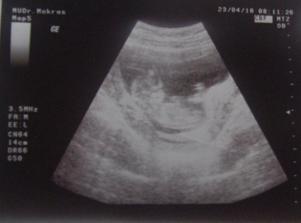

Tehulkovanie 🙂 🙂 🙂